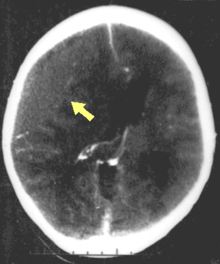

Movement disorders that may develop after TBI include tremor, ataxia (uncoordinated muscle movements), spasticity (muscle contractions are overactive), myoclonus (shock-like contractions of muscles), and loss of movement range and control (in particular with a loss of movement repertoire).[31][33] The risk of post-traumatic seizures increases with severity of trauma (image at right) and is particularly elevated with certain types of brain trauma such as cerebral contusions or hematomas.[34] People with early seizures, those occurring within a week of injury, have an increased risk of post-traumatic epilepsy (recurrent seizures occurring more than a week after the initial trauma).[35] People may lose or experience altered vision, hearing, or smell.[24]

The preferred radiologic test in the emergency setting is computed tomography (CT): it is quick, accurate, and widely available.[80] Follow-up CT scans may be performed later to determine whether the injury has progressed.[27]